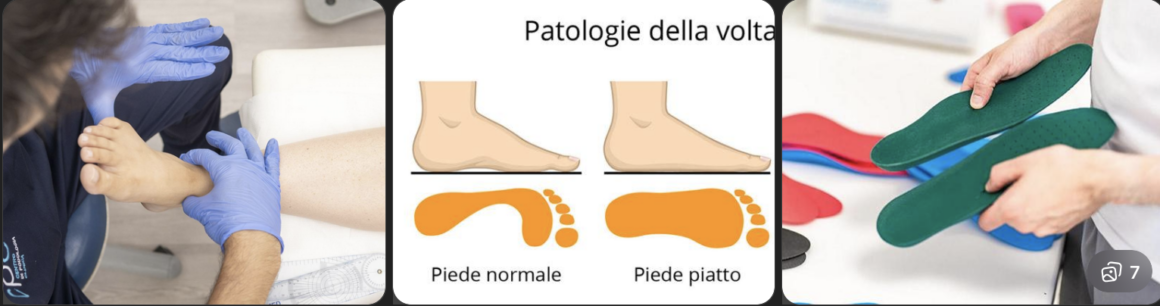

Piede Piatto nell’Adulto a Perugia

Piede Piatto nel Bambino a Perugia

Piede Cavo a Perugia